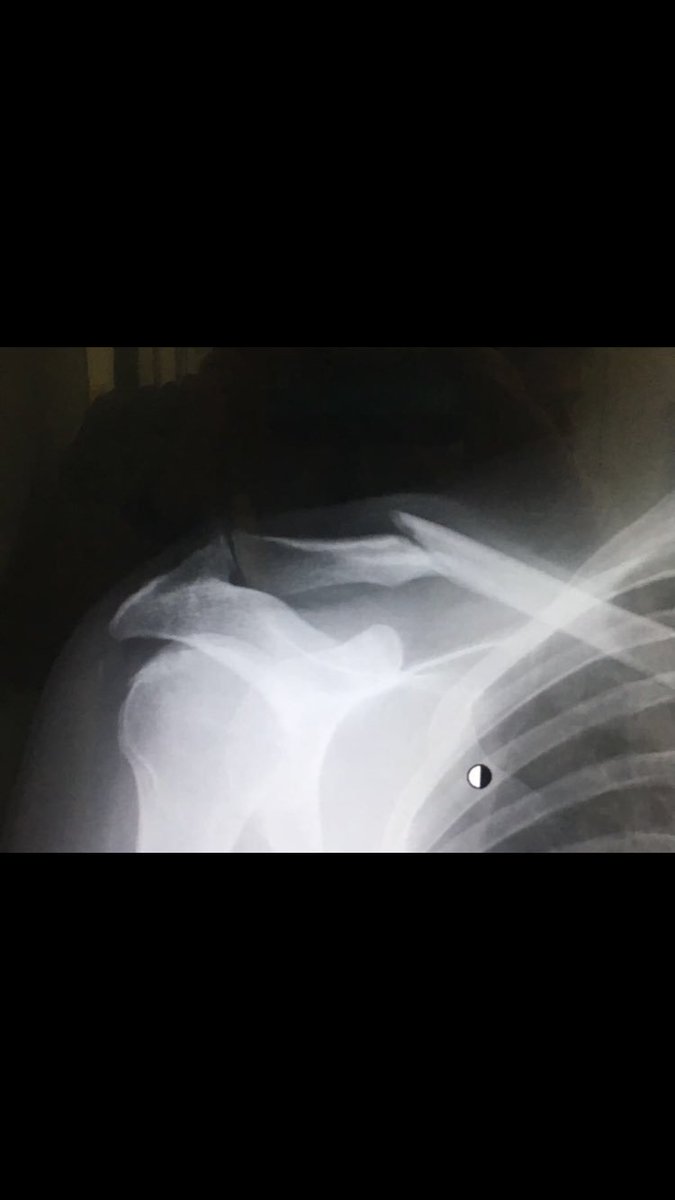

Сколько срастается ключица у детей